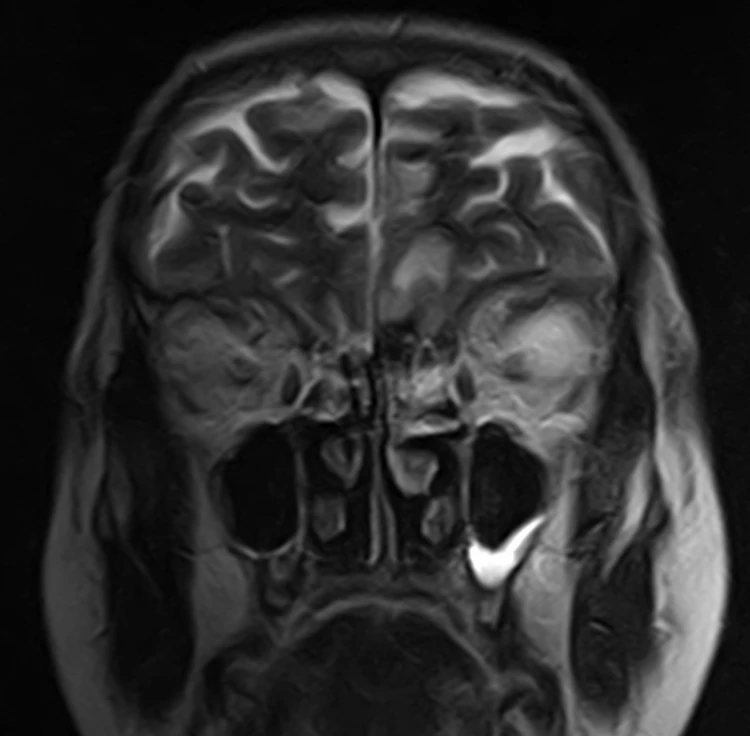

Женщина 32 года. Больной считает себя с 2024 г, когда стала отмечать онемение угла рта. Со слов пациентки ей был предварительно выставлен диагноз - РС, но дополнительных методов обследования и специфического лечения не проводилось. В настоящее время жалоб нет. В исследовании от октября 2024 отмечался очаг в левой затылочной доле с выраженным контрастированием, в настоящее время этот же очаг отмечается с сохраняющимся контрастированием. Формально - есть выполнение критериев диссеминации и в пространстве (юкстакортикальный и перивентрикулярный очаги есть), и во времени (есть усиливающиеся и неусиливающиеся очаги), клиника тоже вполне укладывается. Но! Найти в литературе подобных случаев мне не удалось, видел сам и максимум, что находил в литературе - полгода контрастирования. Получается, мы имеем дело с крайне атипичным рассеянным склерозом, или это не рассеянный склероз. А тогда что? Сосудистая мальформация не вариант - на SWI не видать. Какая-то ганглиоглиома? А другие очаги тогда что? Есть соображения? Кстати, диффузия стойко повышенная, и на б1000 почти не видно (изо). На Т2 не меняется